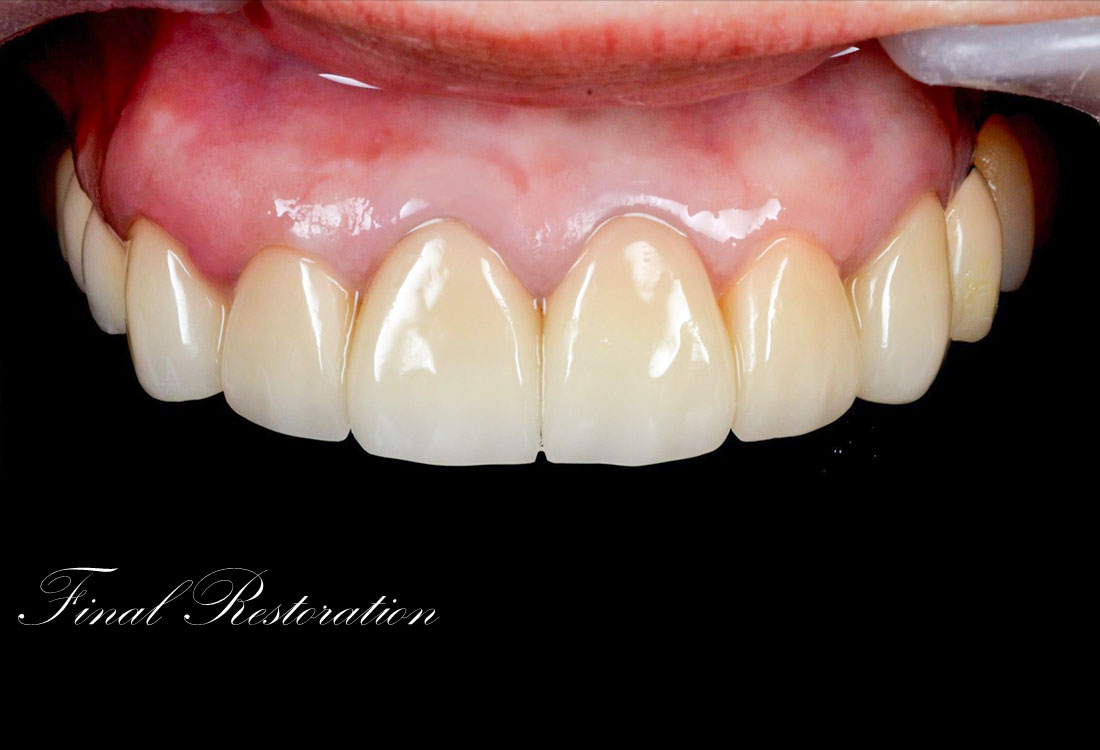

ホワイトニングで全体的に白くした後、その色に合わせて被せ物を作っていきます。

治療後

白く明るい口元になりました。